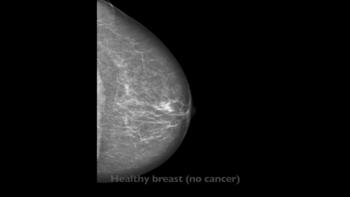

Figure 1. Mammogram of a healthy breast.

Figure 3. Mammogram of healthy breast.